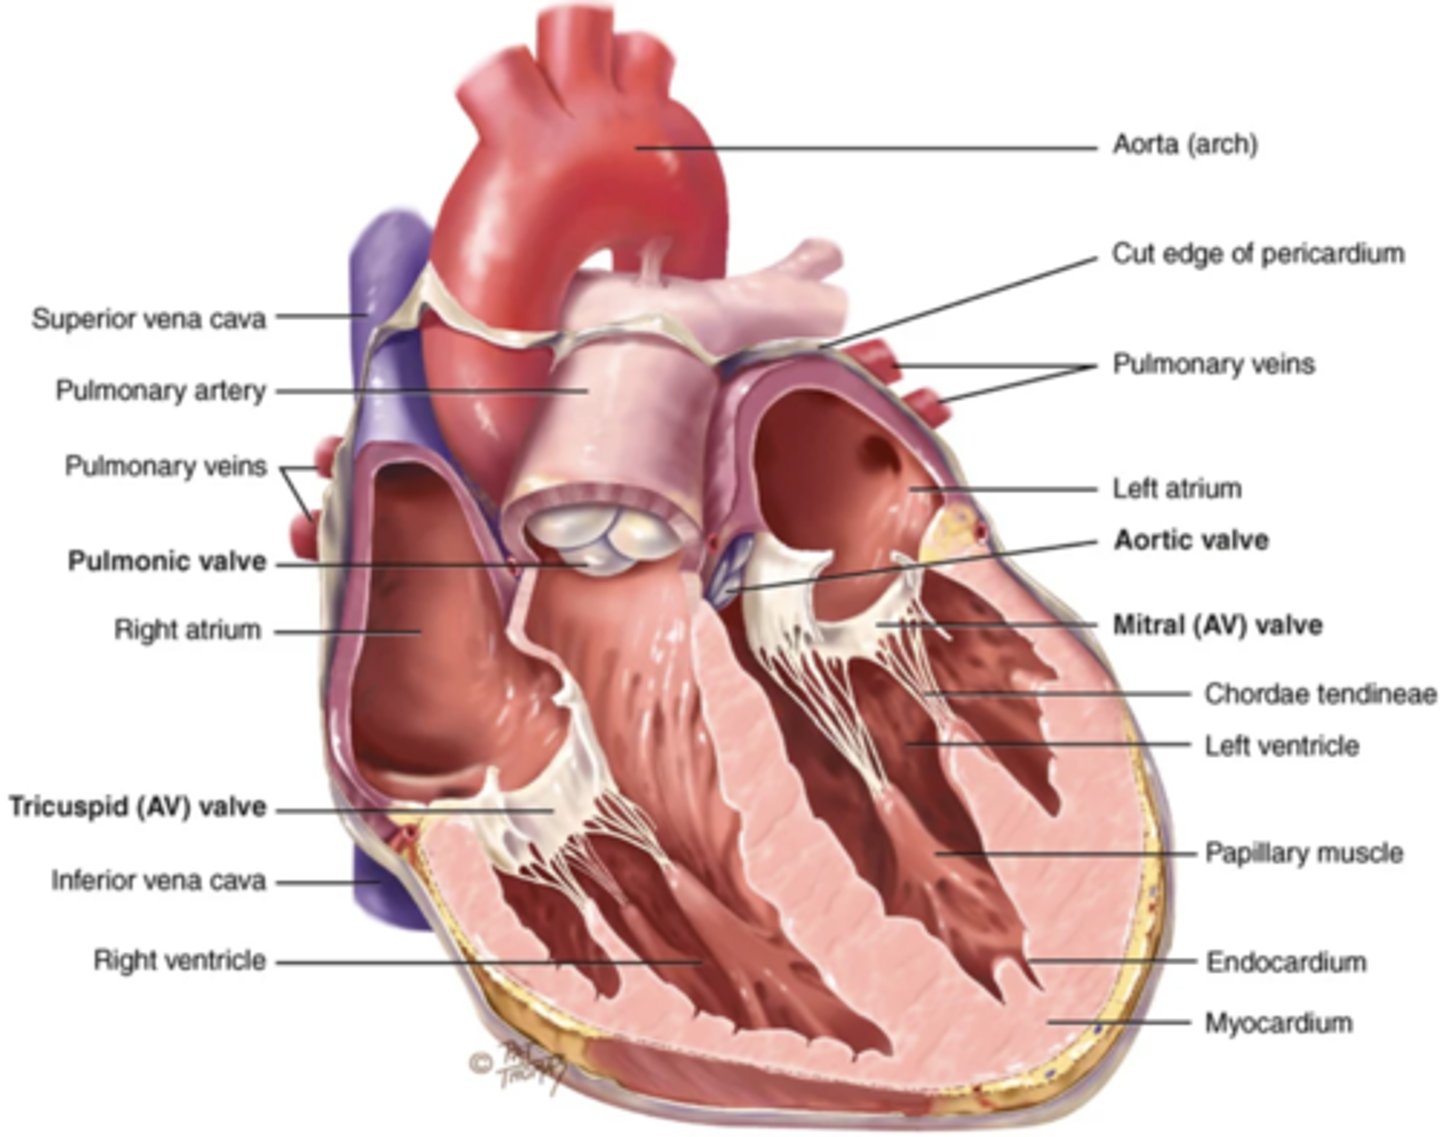

Anatomy of the Heart

3 Layers of the Heart Wall

- Pericardium

- Myocardium

- Endocardium

Pericardium

Myocardium

The muscular wall of the heart; does the pumping

Endocardium

The thin layer of endothelial tissue that lines the inner surface of the heart chambers and valves

2 Types of Chambers in the Heart

- Atrium

- Ventricles

Atrium (2)

A thin-walled reservoir for holding blood, located at the upper chamber of the heart

Ventricle (2)

The thick walled muscular pumping chamber of the heart located at the bottom chamber of the heart

2 Main Types of Valves of the Heart

- Atrioventicular

- Semilunar

Atrioventricular Valves (AV) (2)

The valves that separate the atria and the ventricles

The 2 Atrioventicular Valves of the Heart

- Tricuspid

- Mitral

Tricuspid Valve

- The right AV valve separating the right atrium from the right ventricle

- Connected by 3 chordae tendinae

Mitral (Bicuspid) Valve

- The left AV valve separating the left atrium from the left ventricle

- Connected by 2 chordae tendinae

Chordae Tendinae

Fibers (heart strings) attatched to the tricuspid and mitral valve which pull it closed when papillary muscles contract, preventing back flow of blood

Semilunar Valves (SV) (2)

Valves located between the ventricles and the pulmonary arteries and aorta

The 2 Semilunar Valves of the Heart

- Pulmonic

- Aortic

Pulmonic Valve

The SV valve of the right side of the heart

Aortic Valve

The SV valve of the left side of the heart

The 4 Great Vessels of the Heart

- Superior/inferior venae cavae

- Pulmonary artery

- Pulmonary veins

- Aorta

Superior/Inferior Venae Cavae

The large veins that empty into the right atrium of the heart and return unoxygenated venous blood to the right side of the heart

Pulmonary Artery

Artery carrying oxygen-poor blood from the heart to the lungs

Pulmonary Veins

Veins carrying oxygenated blood from the lungs to the heart

Aorta

The largest artery in the body which carries oxygenated blood from the heart throughout the body